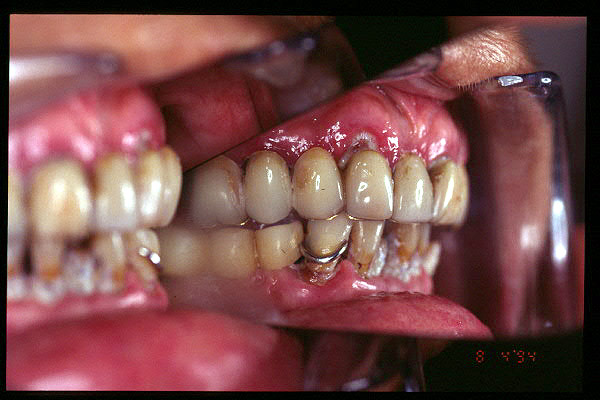

CM Caries, patología periodontal, desgaste.

CM Desgaste por bruxismo, presencia de cálculo